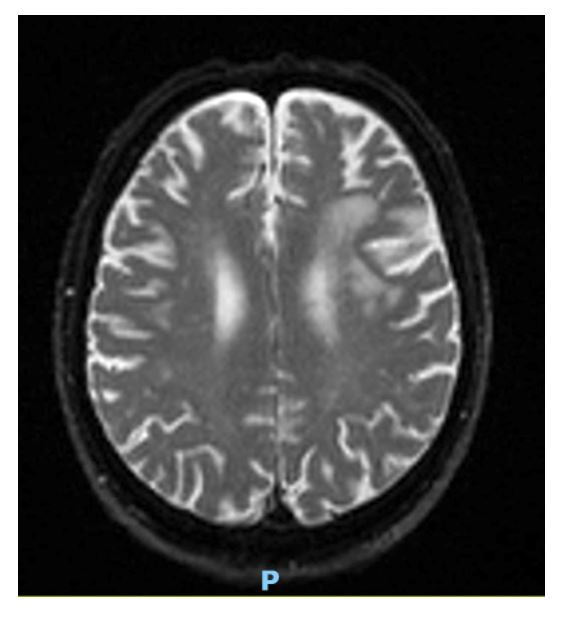

Figure 1: MRI Auto-Diff TRACEW revealing subacute white matter changes in L MCA territory from 4 years prior (2021 imaging).